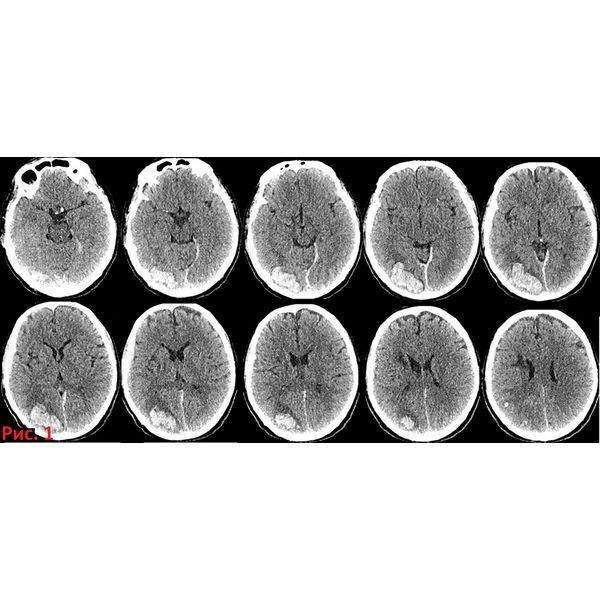

При проведении компьютерной томографии (КТ) головного мозга обнаружили подострую внутримозговую гематому правой затылочной области.

На КТ головного мозга после операции выявили субарахноидальное кровоизлияние на фоне множественных артефактов от имплантированных спиралей и контрастного вещества в субарахноидальном пространстве и цистернах головного мозга.

В течение последующих двух недель динамика была положительная. На 14-й день после эндоваскулярного этапа КТ показала, что геморрагическое и ишемическое повреждение головного мозга уменьшилось.